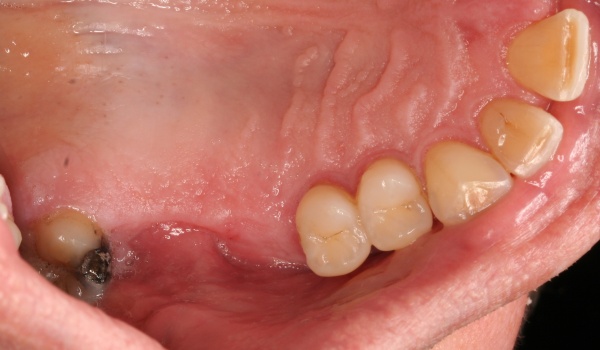

Dies lässt sich exemplarisch auch im folgenden Fall zeigen: Ein männlicher Patient mit der Diagnose einer generalisierten aggressiven Parodontitis (32 Jahre) befand sich zunächst in einer systematischen antiinfektiösen nichtchirurgischen Parodontitistherapie mit begleitender systemischer Antibiose. An der nachfolgenden unterstützenden Parodontitistherapie nahm er jahrelang teil (2007 – heute) und wies eine sehr gute Compliance auf. Im Oktober 2012 erfolgte durch mich die Implantation regio 34. Ein Jahr post implantationem zeigen sich unverändert kein periimplantärer Knochenabbau sowie klinisch gesunde Gingivaverhältnisse und physiologische Sondiertiefen (Abb. 18).